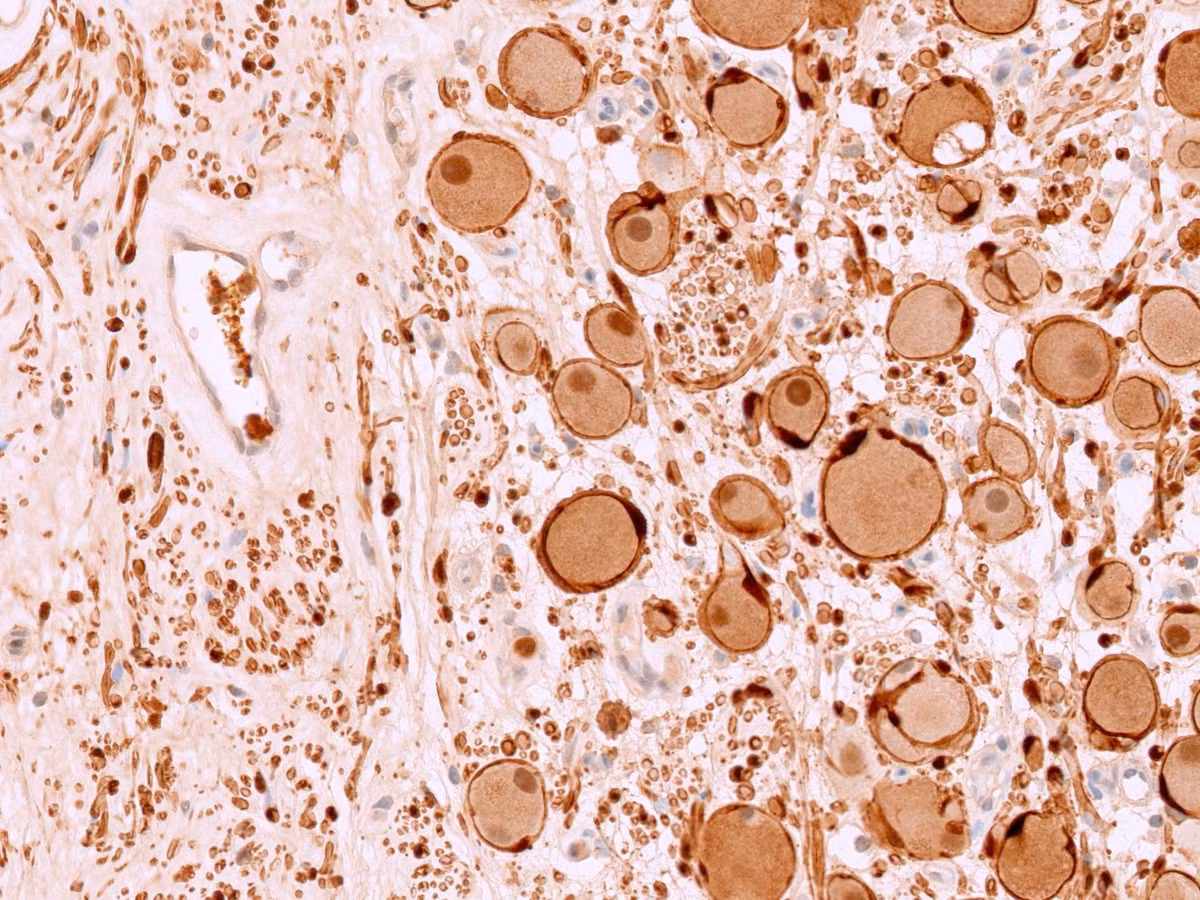

Biểu hiện tế bào của u nguyên bào thần kinh Ganglioneuroblastoma - Ảnh BVCC

Kết quả xét nghiệm là u nguyên bào thần kinh đệm típ đang biệt hóa (Ganglioneuroblastoma). Đây là một loại u thần kinh hiếm gặp, nếu không được phát hiện sớm có thể dẫn đến di căn, khó điều trị và giảm cơ hội sống của người bệnh.